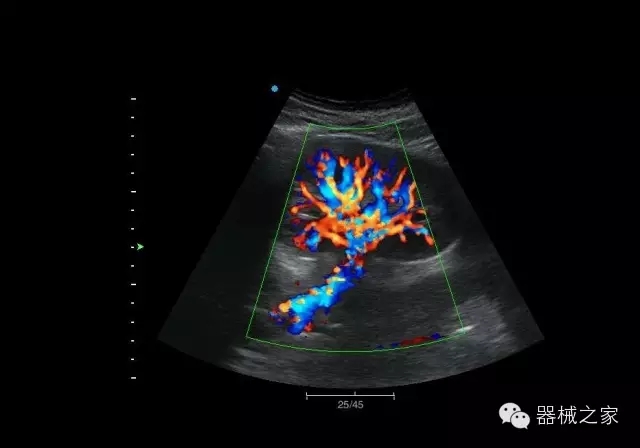

腎臟血流